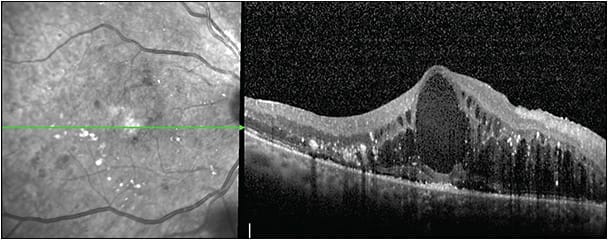

Visual improvement is greatest in patients with subfoveal serous detachment (SRD). Some recent studies have suggested that the effectiveness of DME therapy depends on the preoperative OCT pattern (Figure 1). For example, a greater improvement of vision was detected by Ichiyama et al26 in DME patients with SRD. These results were a little bit worse in patients with mixed forms, and very poor in patients with cystoid macular edema (CME) or patients with sponge-like diffuse retinal thickening (SDRT). Diametrically opposed are the results on the effect of anti-VEGF, which is greatest in the SDRT group, intermediate in the CME and mixed forms, and poor in the SRD group.27 The effectiveness of intravitreal corticosteroid is reported to be greatest in the CME group, intermediate in the SDRT and mixed forms, and weakest in the SRD group.28